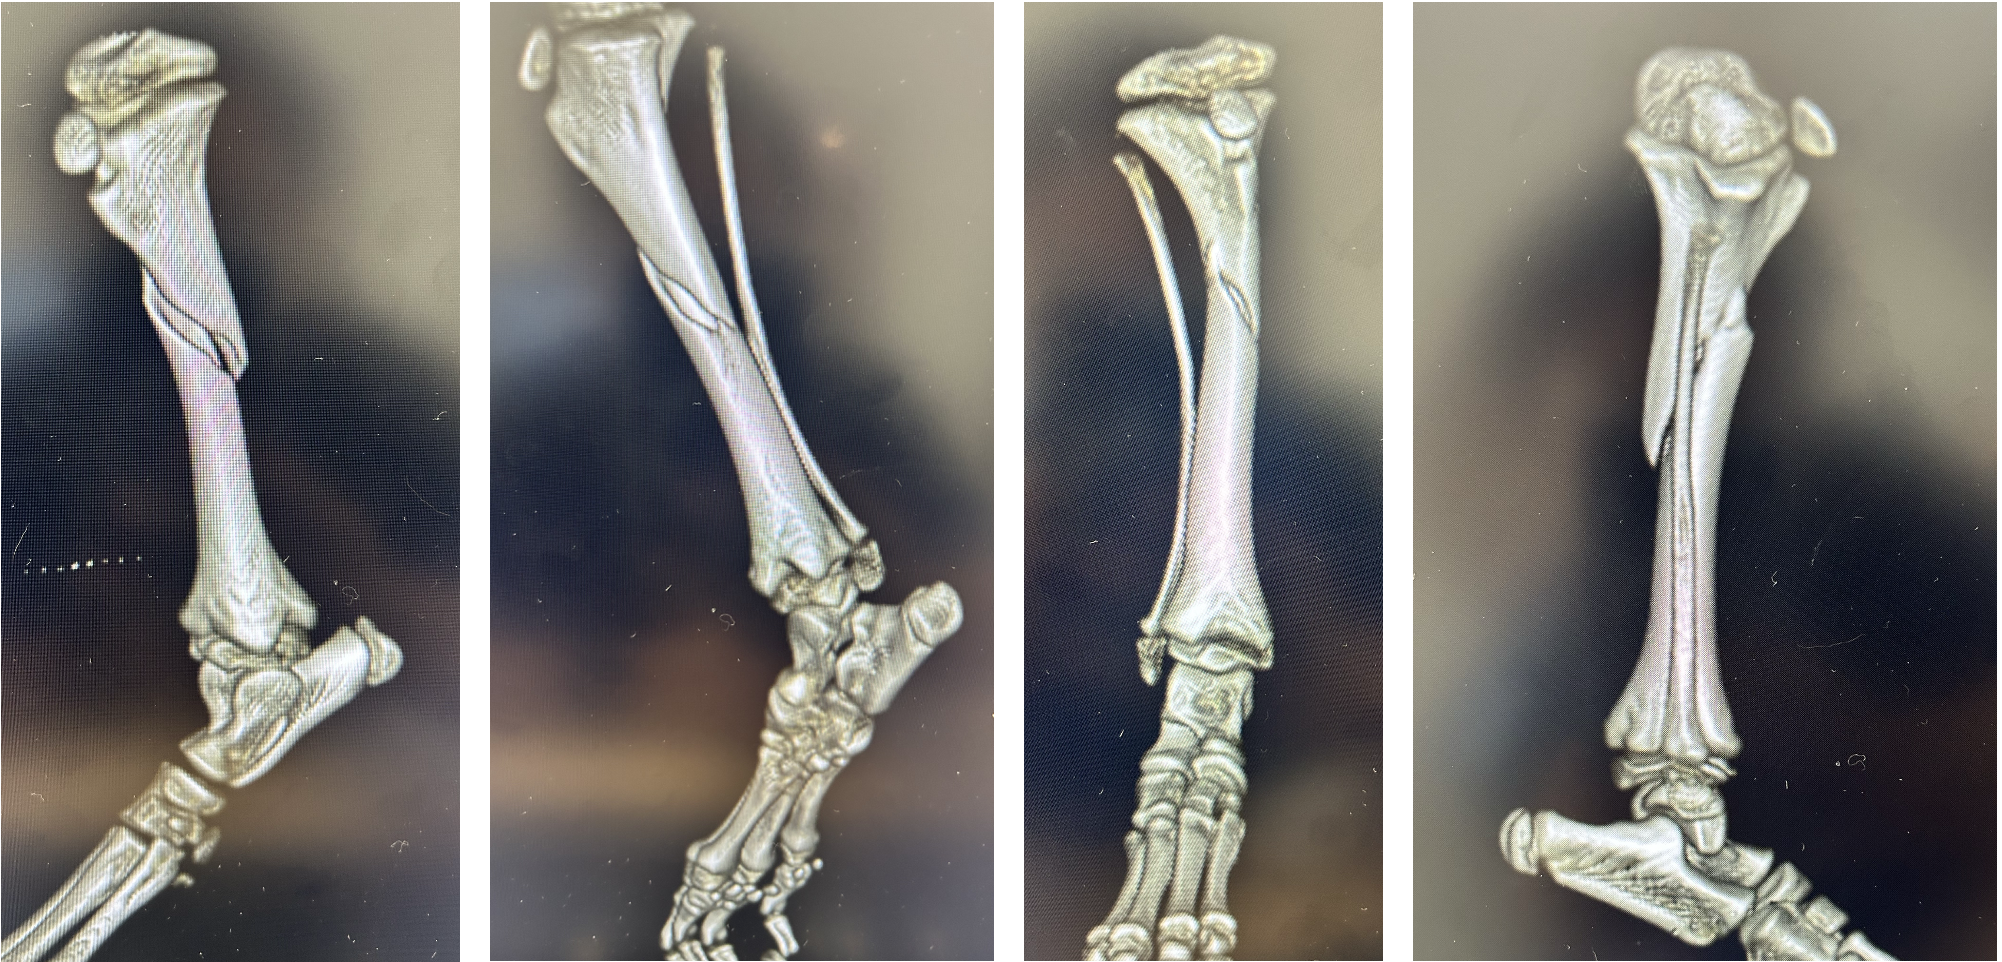

レントゲン、CTより右脛骨の斜骨折または螺旋骨折が認められた

中和プレート固定、ラグスクリュー